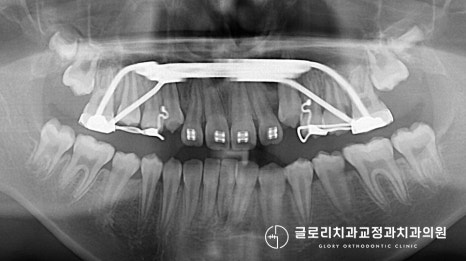

상악골 확장을 동반한

페이스 마스크를 진행하기로 했습니다.

아직 영구치가 자라기 전이라

전체적인 치열 개선보다는

거꾸로 물리는 4개의 앞니만

우선적으로 치료하기로 했습니다.

앞서 계획했던 대로 개선을 돕고 있는 모습입니다.

좁은 악궁을 넓혀준 뒤, 상악의 전방 성장을 유도하고

하악의 성장을 막았는데요.

이런 원리로 진료를 진행했더니

다행히 올바른 교합으로 바뀌었습니다.